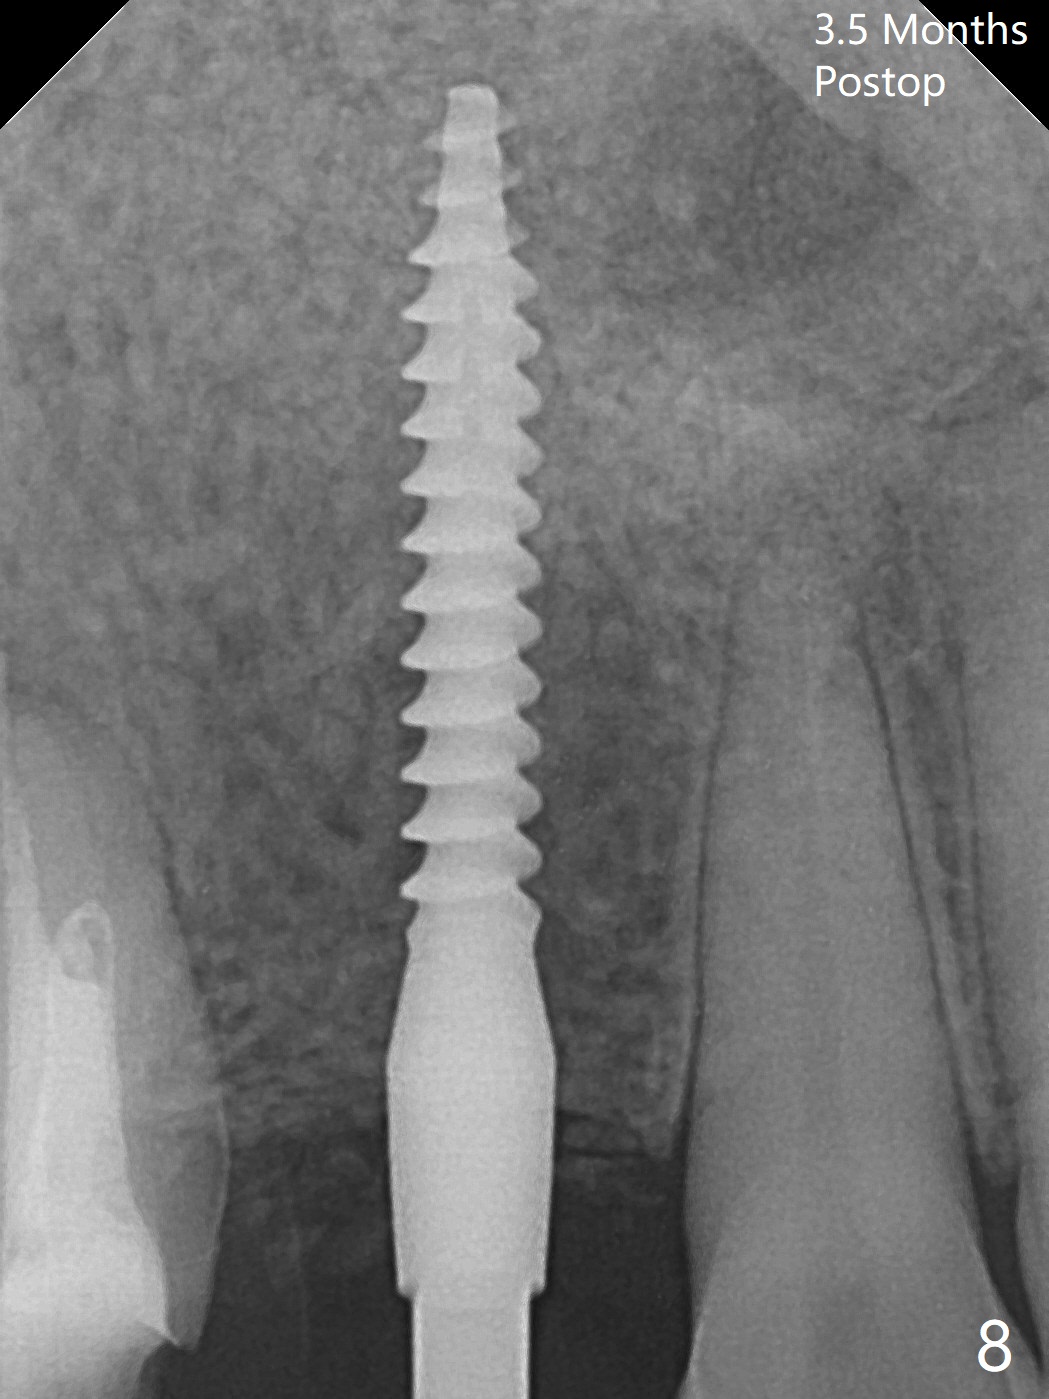

Osteotomy starts with guide and 2.2 mm drill for initial 3.5 mm palatal. A semilunar incision is made buccal to remove the impacted canine (#6 by sectioning). With direct vision buccal and palatal, the final osteotomy is finished free hand with 1.2 and 1.5 mm drills. Initially buccal perforation occurs, the osteotomy route is corrected later (Fig.1). When a 2.5x15 mm 1-piece implant is being placed, it perforates into the buccal concavity again. After redirection, the trajectory seems to be acceptable (Fig.2: CT coronal section). Three coronal implant threads are exposed partially palatal (Fig.3: CT 3-D palatal view). The implant is then turned 2-3 times with insertion torque reaching 40 Ncm. The incision is closed with suture following Osteogen plug placed in the most coronal portion of the socket (Fig.4 P) and allograft (*) in the remaining socket around the apical portion of the implant as well as palatal. The incision does not heal 1 month postop (Fig.5). PRF membrane will be placed next visit. Next visit the wound in fact is healing (Fig.6). PRF is unnecessary. The patient will return for impression 3 months postop. To be cosmetically pleasing, prepare local anesthetic and Laser for gingivectomy (Fig.7 red curved line). There is no bone loss around the implant 3.5 months postop (Fig.8). With topical, minor gingivectomy with laser creates papillae mesial and distal to the implant (Fig.9, 10 (incisal view)). After reline, there is appearance of a canine (Fig.11). The patient returns for impression 5 months postop; there is bone around the apex of the implant (Fig.12 *). The hard and soft tissues remain healthy when final restoration is delivered (Fig.13,14). The buccal plate reforms and #6 socket heals 12 months postop (6 months post cementation, Fig.15). The gingiva remains healthy at #4-6 nearly 2 years post cementation (Fig.16).